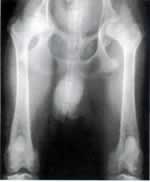

• Dispasia de la cadera (malformacion el la articulación de la cadera)

• Displasia de codo (anormal desarrollo de la articulación)

• Panosteitis (Problema de los husos y cartilagos)

• Osteocondrítis (Cojera causada por variaciones en la densidad del hueso)